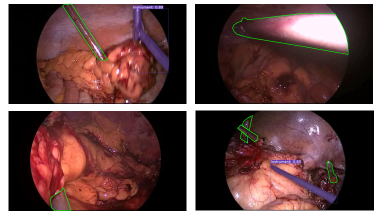

Notably, our top model produces high-quality and temporally consistent masks. Figure 4 shows some examples with varying types and number of instruments together with their respective ground truth annotations. The model is robust to occluded instruments and various harsh conditions, like blood, smoke, and poor lighting. Nevertheless, it struggles with transparent instruments and small instruments on the edge of the field of view. Figure 5 illustrates some examples of challenging frames for our proposed algorithm, which we will seek to address in future work.